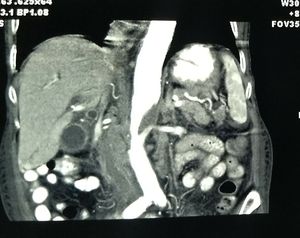

Ct of a 71 yr old woman with ca stomach.... Can anyone tell about a significant finding seen in this film